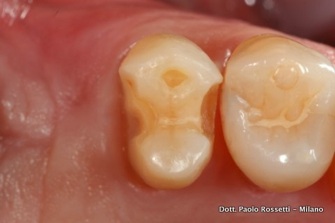

La paziente, 35 anni, richiede la sostituzione dei denti mancanti, ma rifiuta categoricamente l'idea di sottoporsi alla chirurgia implantologica. La scelta ricade sulla protesi a ponte, ma la ragazza desidera che i denti che sostegono il ponte vengano ridotti il meno possibile. Si opta per un ponte su intarsi, con minima asportazione del tessuto dentale sano. Dai denti-pilastro sono state rimosse solamente le vecchie otturazioni.